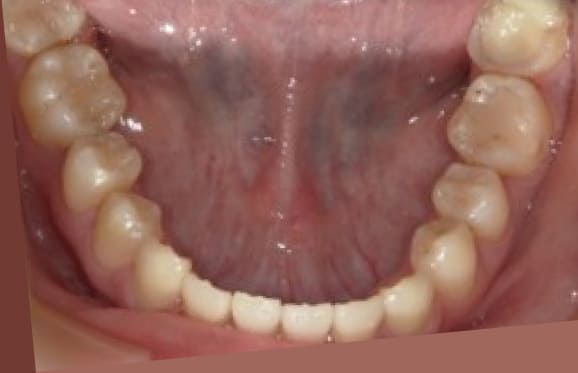

● 歯根が折れ保存不可の歯を抜歯して、そのスペースに八重歯を並べた症例

藤沢デンタルオフィスの虫歯や破折で抜歯後の部分矯正